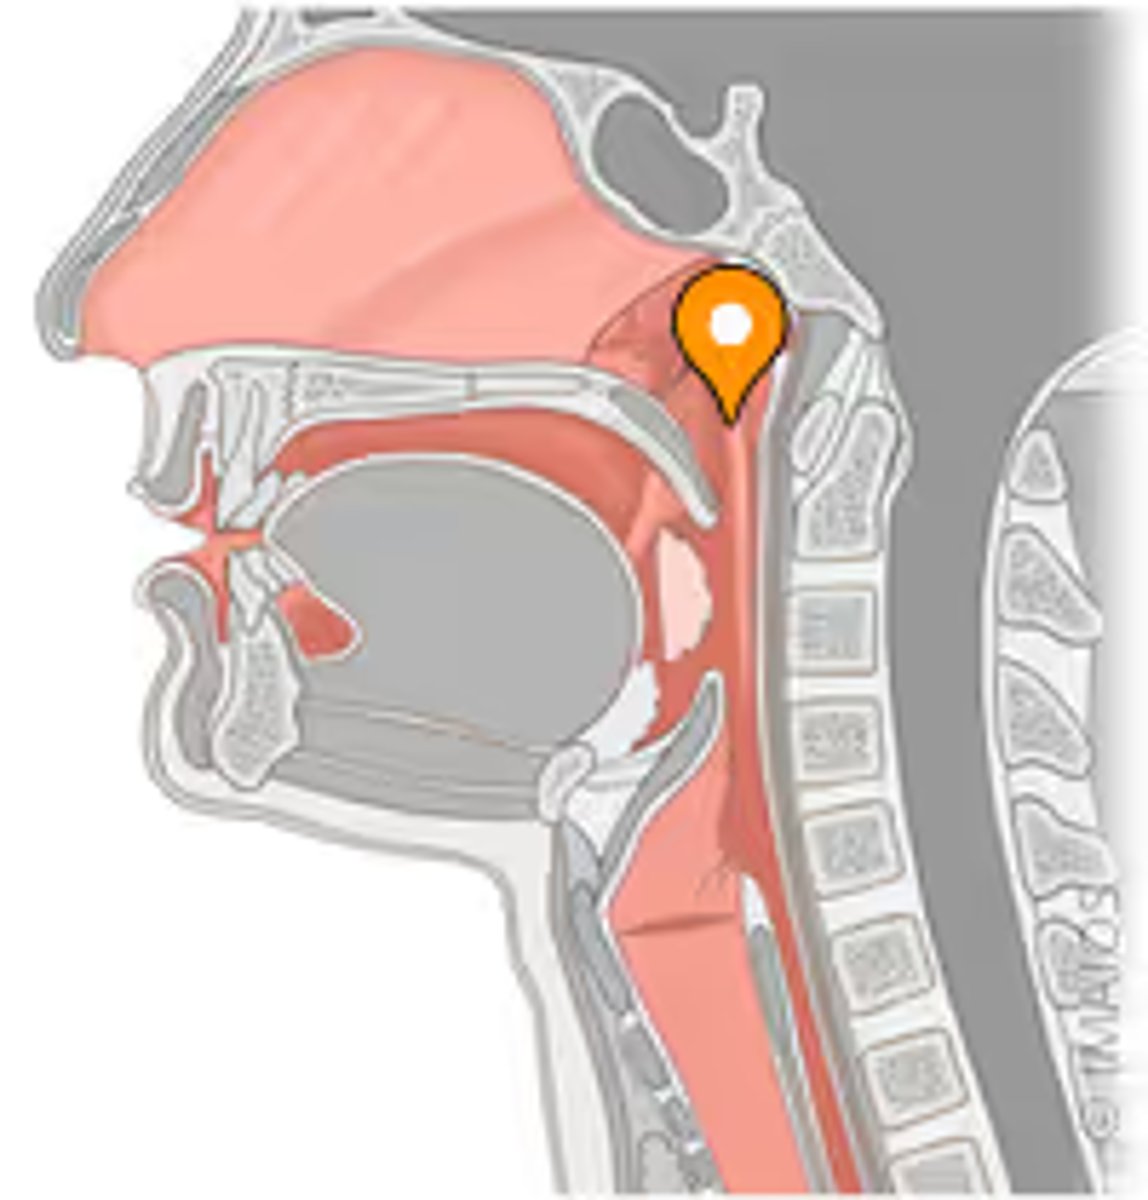

pharyngeal tonsil

tonus tubaris

opening of pharyngotympanic tube

salpingopharyngeal fold

uvula